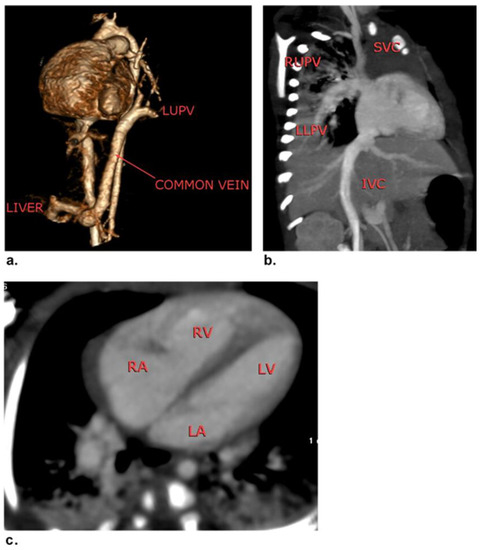

3.1. Patients and CHDs

| Extracardiac Total anomalous pulmonary venous return Aortic coarctation Patent ductus arteriosus Double aortic arch Supravalvular aortic stenosis Pulmonary artery stenosis Pulmonary atresia Coronary artery anomalies | 4 (5.9) 6 (8.8) 10 (14.7) 1 (1.5) 3 (4.4) 7 (10.3) 3 (4.4) 4 (5.9) |